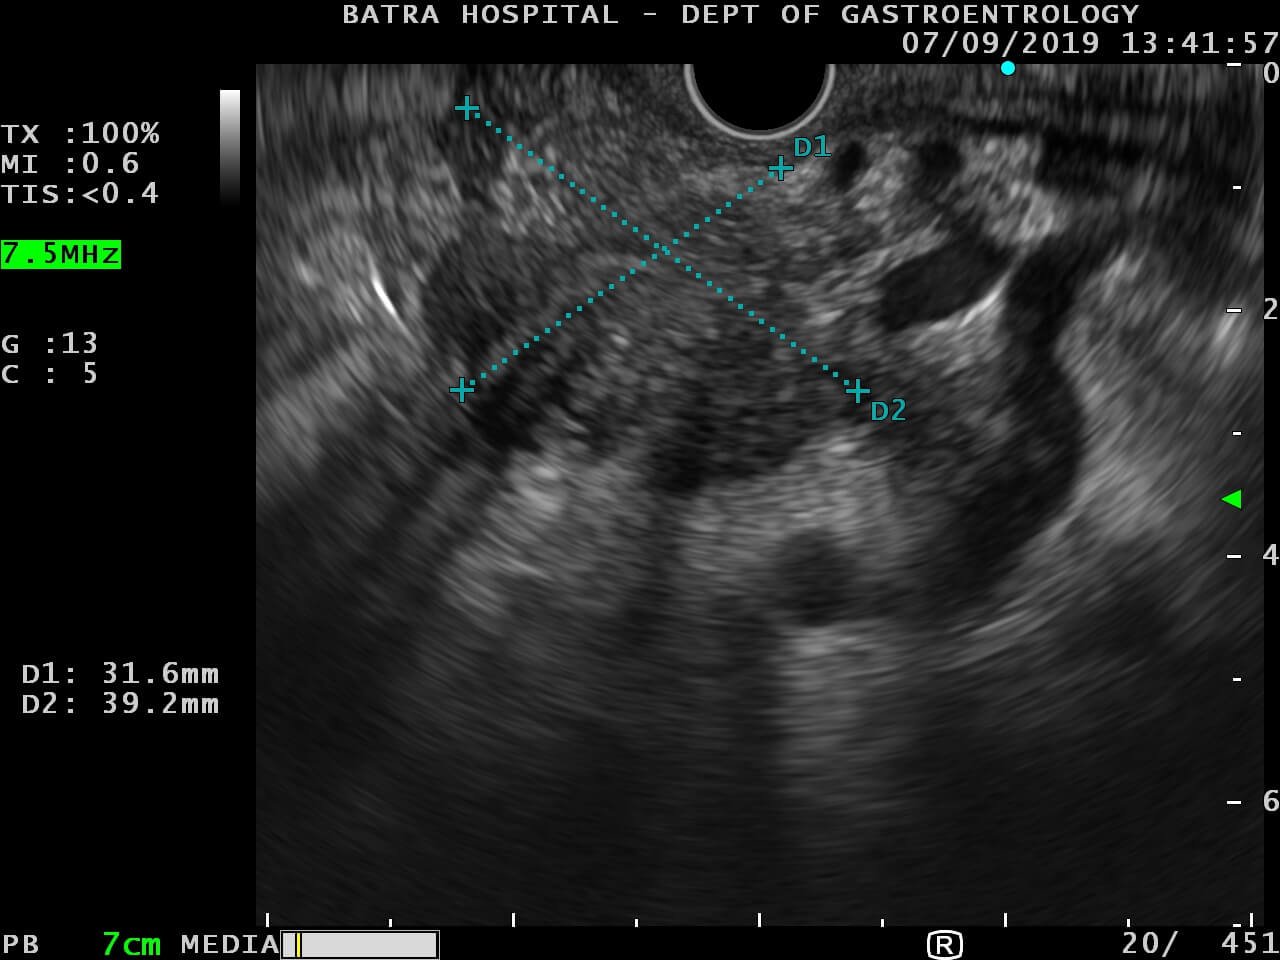

Endoscopic ultrasound or echo-endoscopy is a medical procedure in which endoscopy is combined with ultrasound to obtain images of the internal organs in the chest, abdomen, and colon. It can be used to visualize the walls of these organs or to look at adjacent structures.

EUS is an ultrasound of internal structures surrounding the GI tract with the help of an endoscope. It provides excellent resolution of the pancreas, biliary system, and the mediastinum. EUS is performed by oral route after conscious sedation. During the procedure, samples can be taken from the nodes in the mediastinum, tumors of the pancreas, and bile duct. With the help of endoscopic ultrasound, various collections can be drained internally into the stomach or rectum, and in many cases, major surgeries can be avoided. Consulting an experienced endoscopy specialist in Faridabad ensures precise diagnosis and effective treatment planning using this advanced procedure.